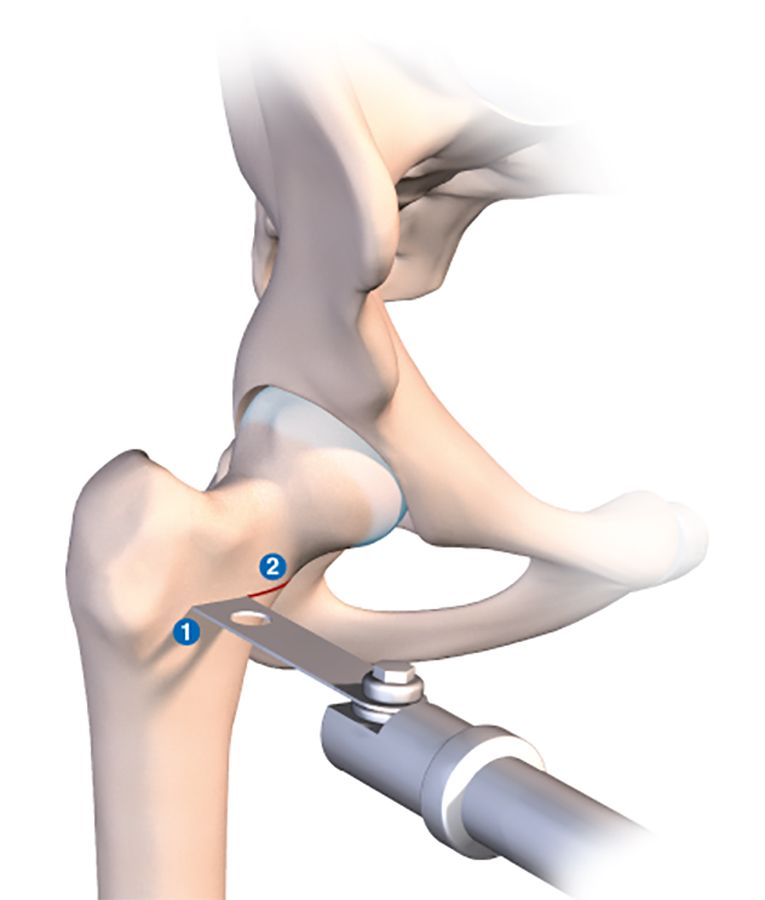

The osteotomy line is usually situated at the base of the neck. It should be as horizontal as possible to improve postoperative stability and avoid any slipping or instability (Fig. 2a).

For a varus-producing osteotomy, a wedge can be removed from the medial base, matching the desired angle of correction. The higher the line, the more accurate the wedge calculations must be because it is all to easy to exaggerate the valgus correction by having the line too close to the neck. The preoperative planning must be just as meticulous as for the traditional technique. We use new computer tools to simplify and even simulate this type of surgery.

In principle, I suggest having the first line as horizontally as possible, then placing the second line above the first to create the osteotomy wedge. The wedge should be incomplete and should not entirely section the lateral femur by the greater trochanter. The cancellous bone in this region will naturally break more towards the top in general. Simply stop the oscillating saw halfway between the lateral and medial cortex, just at the point of insertion of vastus lateralis beneath the trochanteric tubercle. The orthopaedic table is then put in pulse mode, and the open osteotomy line will close fairly naturally. If there is any resistance, the line can be completed laterally using a chisel in order to encourage the fracture towards the greater trochanter.

At no point should the gluteal muscles or fascia lata be involved, and by remaining intact these muscular/aponeurotic structures will act as a lateral tension band.

This osteotomy is easy to repair, using the same technique as for a normal badly impacted fracture of the base of the neck of femur, with two or three large diameter cannulated screws.

Just before using the orthopaedic table to begin the compression, it is a good idea to use a tibial drill guide (as for cruciate ligament repair) (Figs. 2b, c, d).